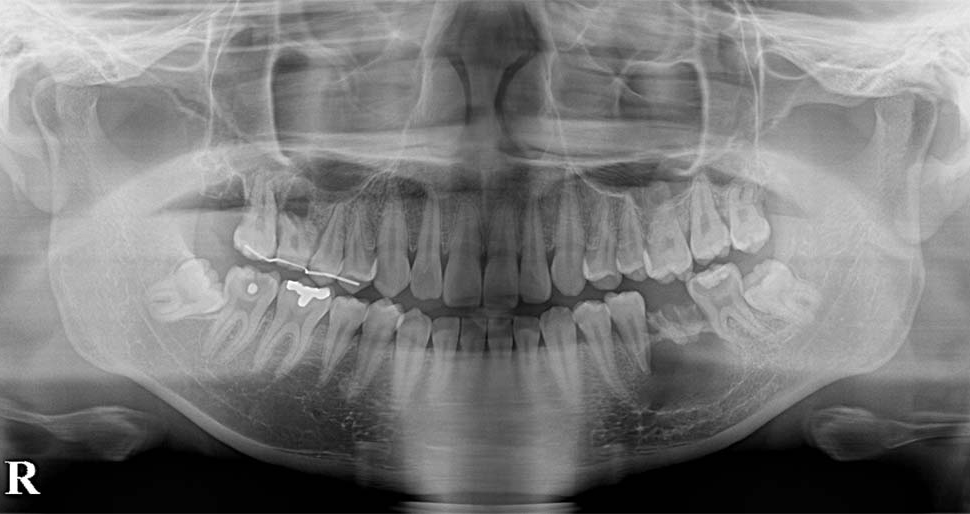

40代男性

ケース1:左下の歯が痛い

親知らずが隣の歯と重なり虫歯になった患者さんです。

他県の歯科医院より紹介頂き受診されました。初診の当日に処置を行っています。

歯の頭の部分を削って抜きました。切開は行っていませんが2糸縫って終わっています。

術後は紹介先で経過を診て頂いていますが、少しの腫れはあったようですがその他は特に問題はなかったようです。